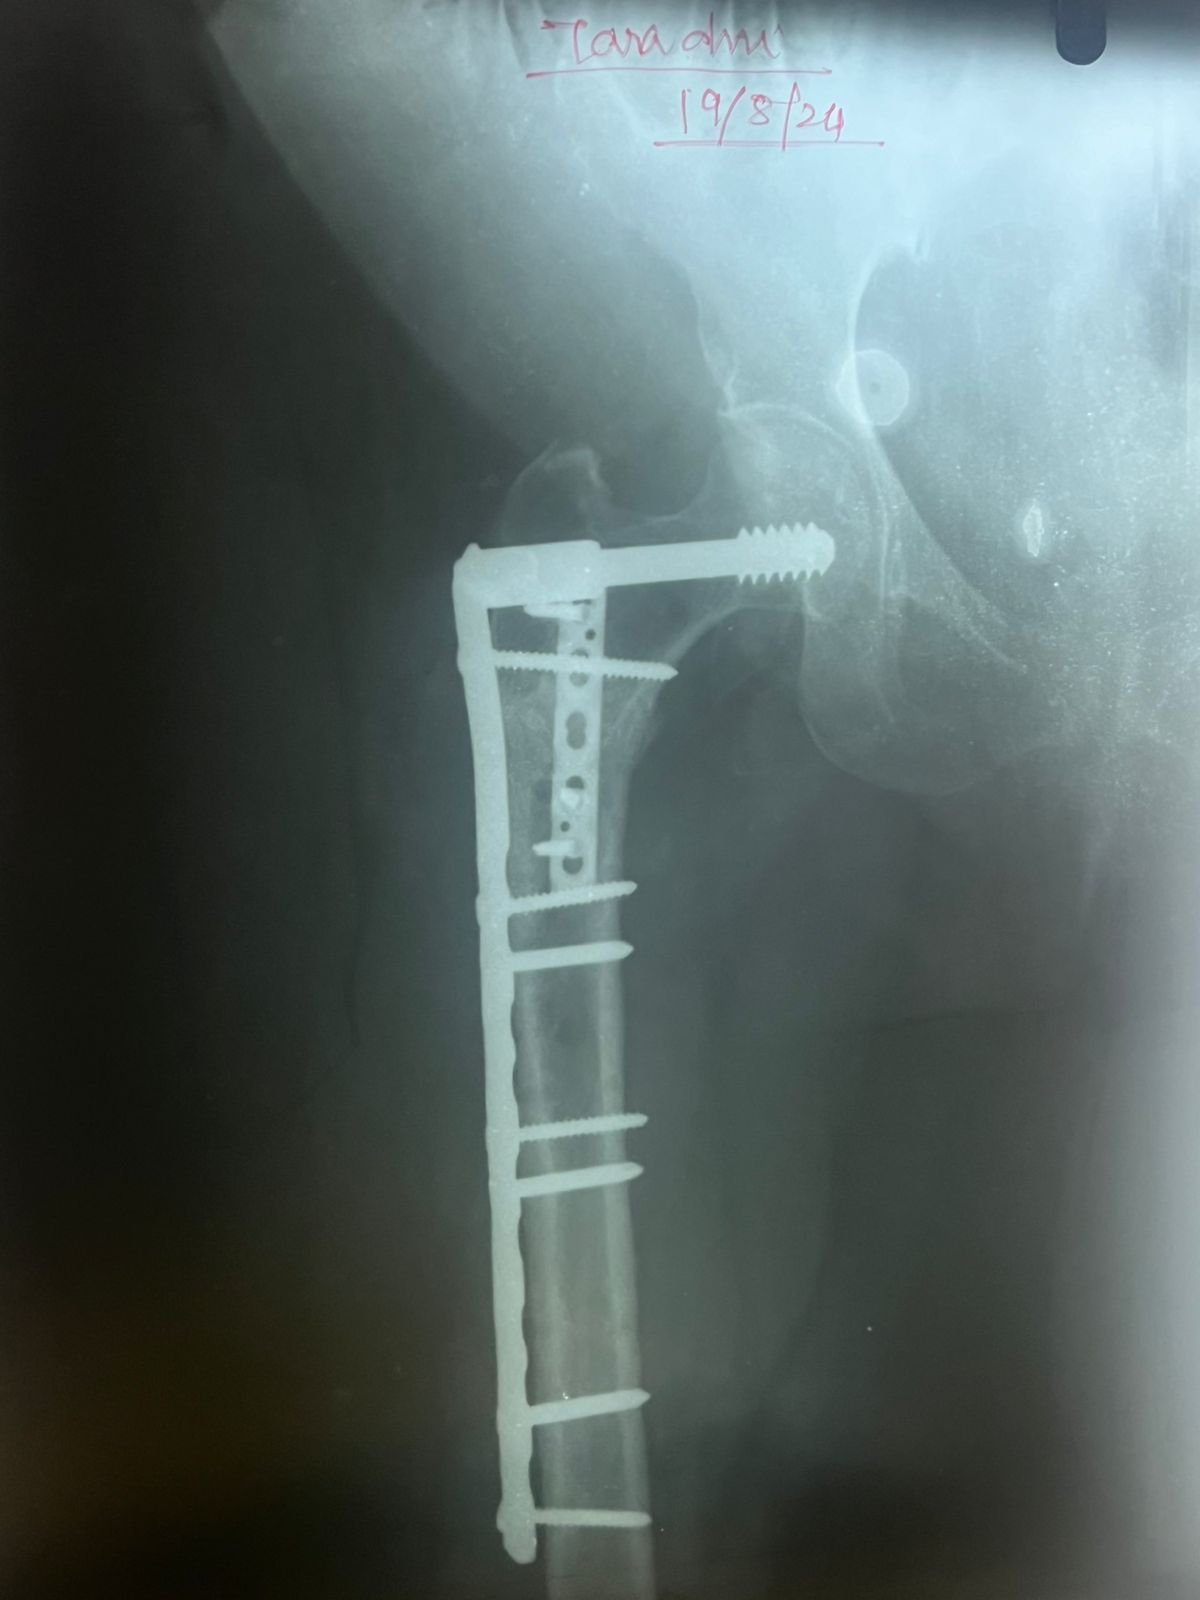

Non union with Broken DCS implant & revision

correction surgery